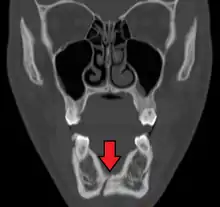

Computed tomography is the most sensitive and specific of the imaging techniques. The facial bones can be visualized as slices through the skeletal in either the axial, coronal or sagittal planes. Images can be reconstructed into a 3-dimensional view, to give a better sense of the displacement of various fragments. 3D reconstruction, however, can mask smaller fractures owing to volume averaging, scatter artifact and surrounding structures simply blocking the view of underlying areas.

| 3D computed tomographic image of a mandible fracture in two places. One is a displaced right angle fracture and the other is a left parasymphyseal fracture. | |